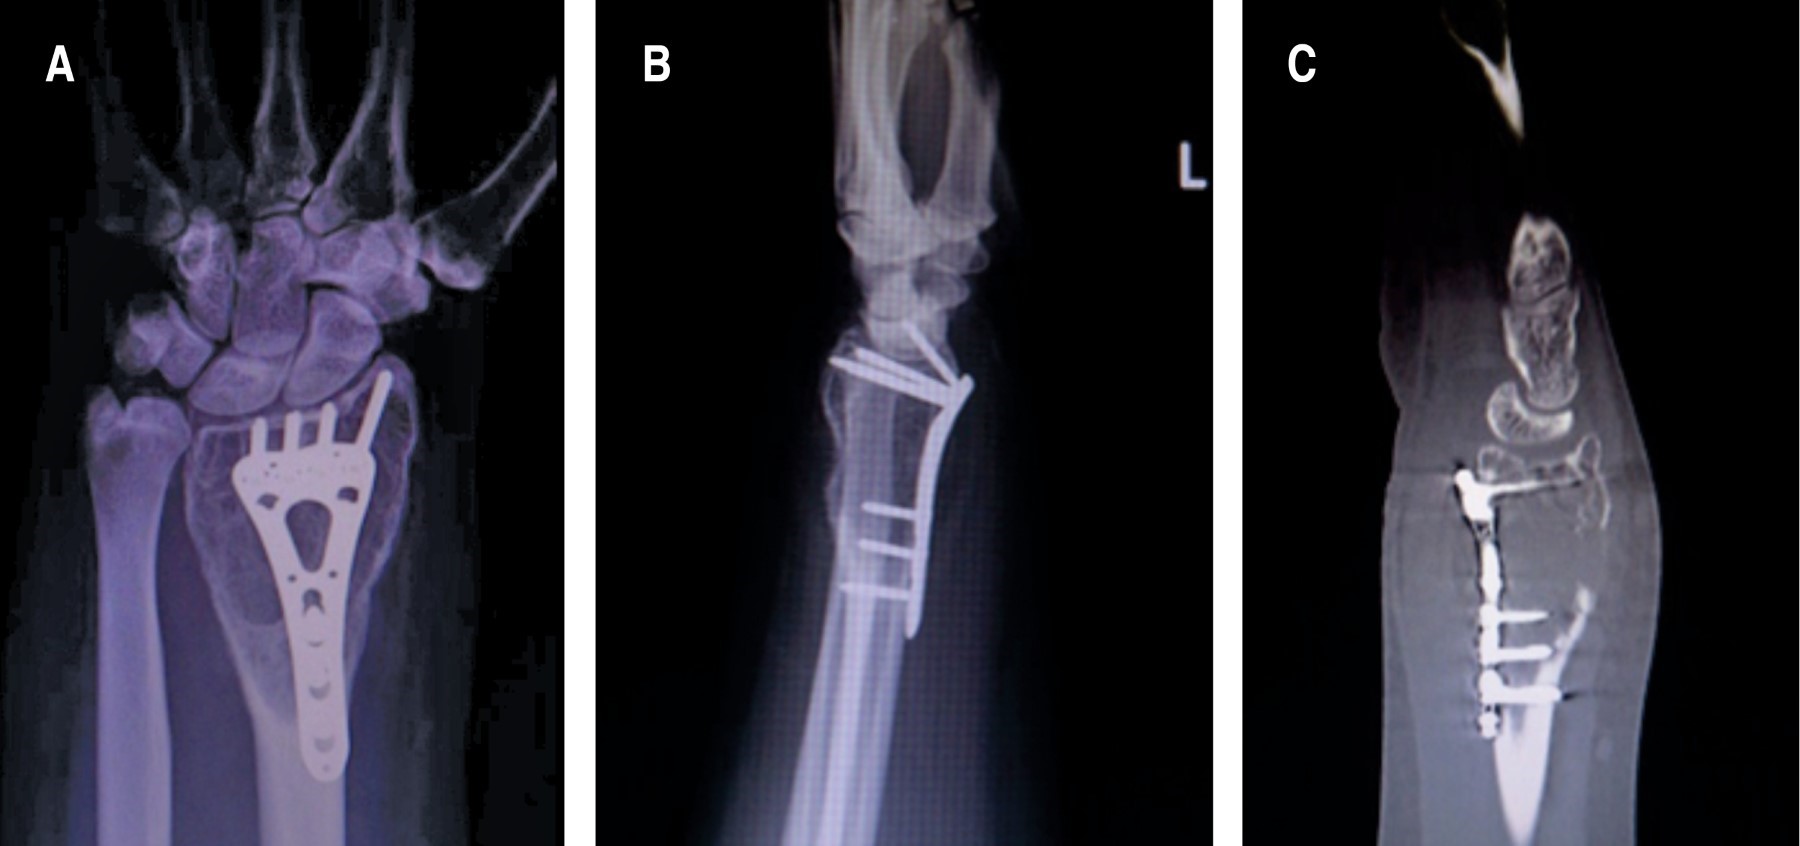

El callo perióstico se observó en radiografías a las seis semanas postquirúrgicas, con una consolidación a los ocho meses, mientras que la remodelación completa se logró a los 11 meses (Figura 6). La paciente recuperó los rangos de movilidad completos del antebrazo y dedos sin dolor a los cinco meses postoperatorios, y la fuerza (medida con dinamómetro) se igualó a la contralateral a los 12 meses con un puntaje DASH de 35.3 (Figura 7).